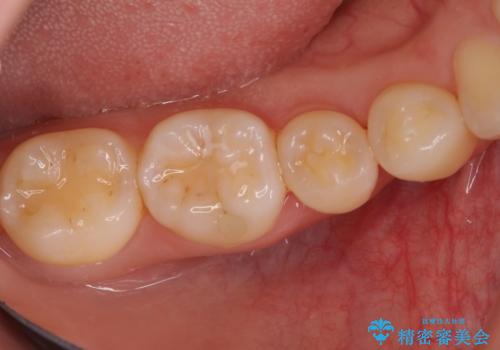

患者様は、他院で右下の歯を抜歯かもと言われました。全体の歯周病はなく、右下の1歯だけ骨が極端に減少していました(初診時歯周ポケット7mm。通常は3mm以下。)。その歯だけ咬合が強いことが原因と考えられたため、咬合を弱くする処置と減少した骨を再生する処置が必要になりました。

骨の再生治療手術をして10か月経過観察をしたのち、骨を平坦化する手術を行い、治療終了となりました。